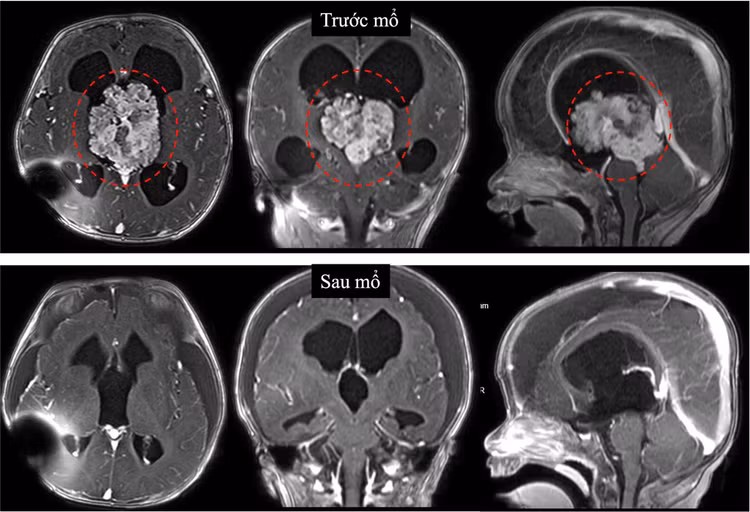

Hình ảnh cộng hưởng từ sọ não ghi nhận khối u vùng não thất III gây chèn ép dẫn đến não úng thủy tắc nghẽn. Khối u nằm vị trí não thất III, vị trí sâu với nhiều cấu trúc thần kinh quan trọng xung quanh, là một trong những vị trí can thiệp rất khó trong phẫu thuật sọ não.

Hình ảnh khối u bệnh nhi được lấy gần hoàn toàn trên phim sau mổ - Ảnh BVCC

Theo TS.BS Trần Minh Huy, Khoa Ngoại Thần kinh, Bệnh viện Nhi đồng 1: “Đây là một ca mổ khó khăn. Vị trí não thất III là một vị trí sâu, trung tâm của não bộ với nhiều cấu trúc thần kinh và mạch máu quan trọng xung quanh. Khối u kích thước lớn (6cm), tăng sinh mạch máu nuôi, phát triển trong lòng não thất III là thách thức lớn cho phẫu thuật viên.